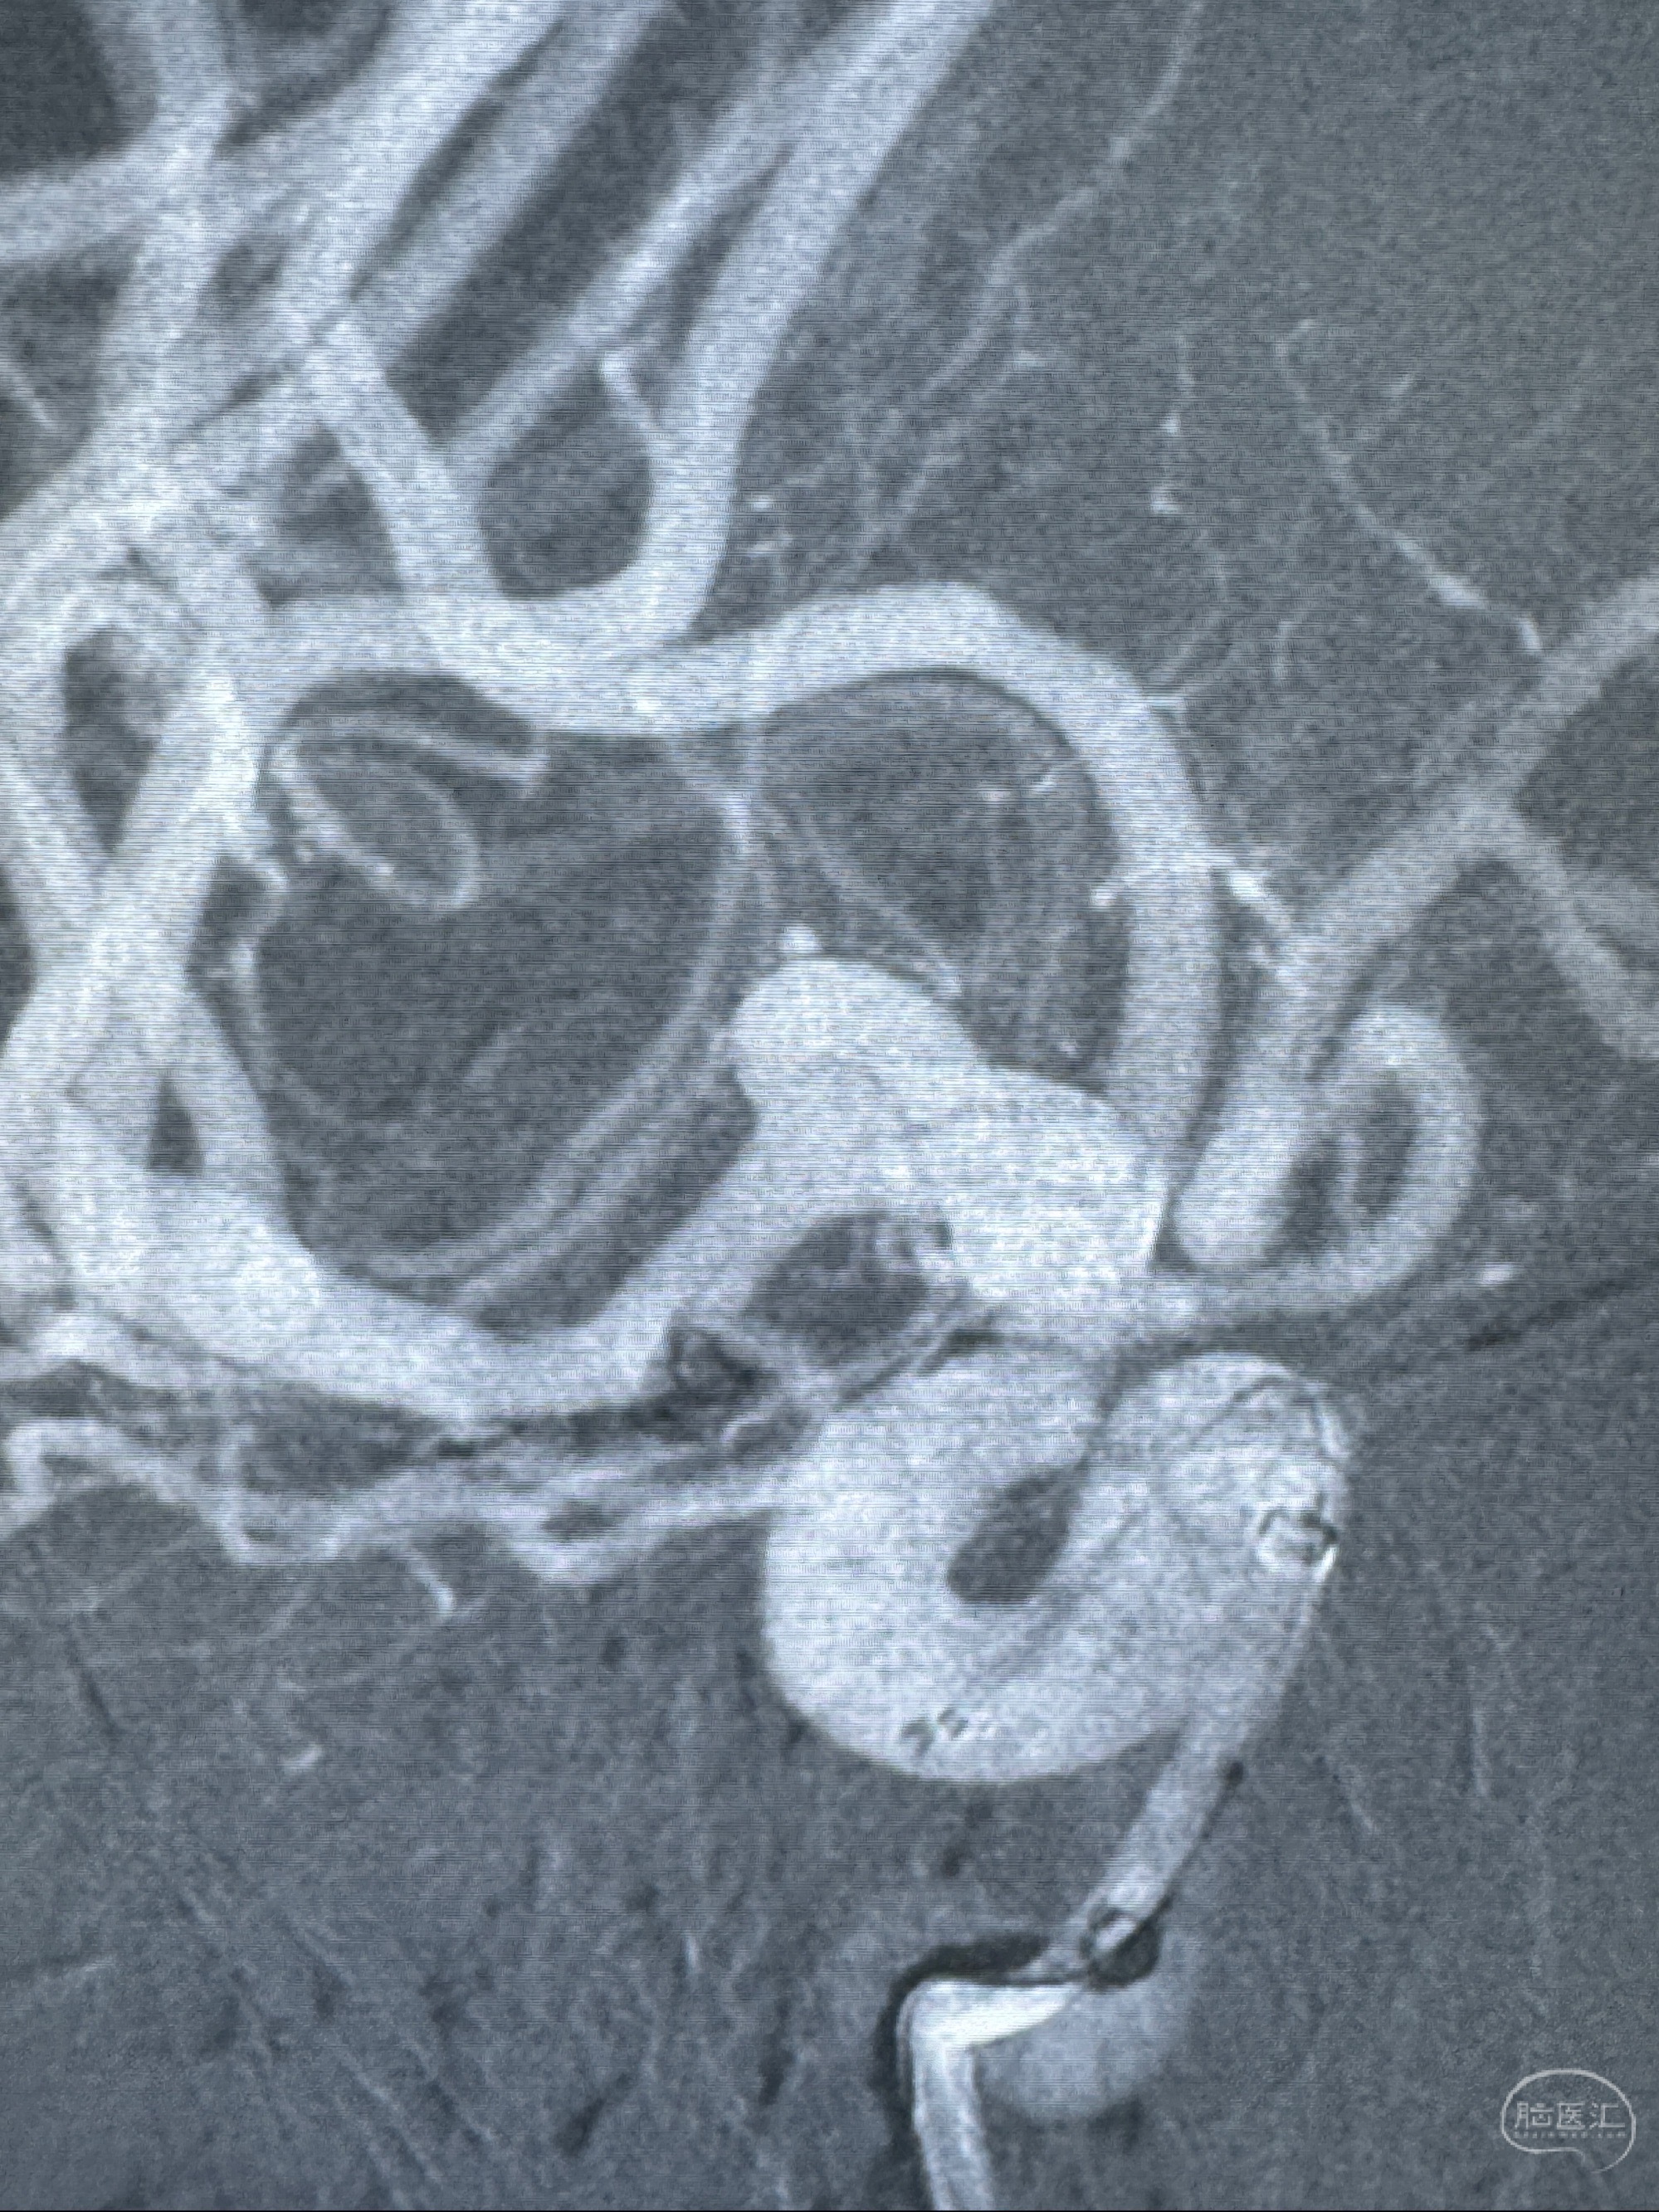

2023-11-24DSA:右侧大脑中动脉下干起始部动脉瘤,约2.3*2.5mm,形态规则

2023-12-04全麻下行支架辅助治疗

S-AB4-20mm